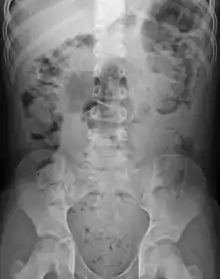

Abdominal X-rays are generally only performed if bowel obstruction is suspected, may reveal extensive impacted fecal matter in the colon, and may confirm or rule out other causes of similar symptoms.[25][17]